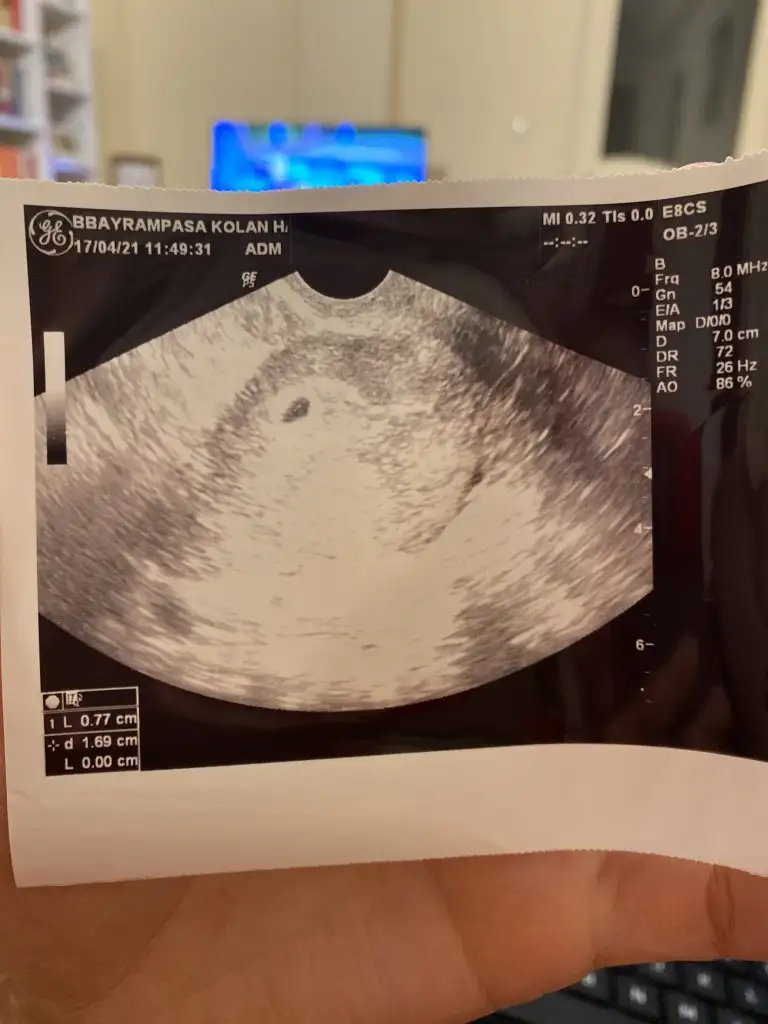

Kızlar selam. Benimde çok erken olacak ama bir tahminiz var mıı 6 hafta 6 günlük şu an ilk attığım foto vajinal diğeri karın bunlardan cinsiyet anlaşılır mı😀